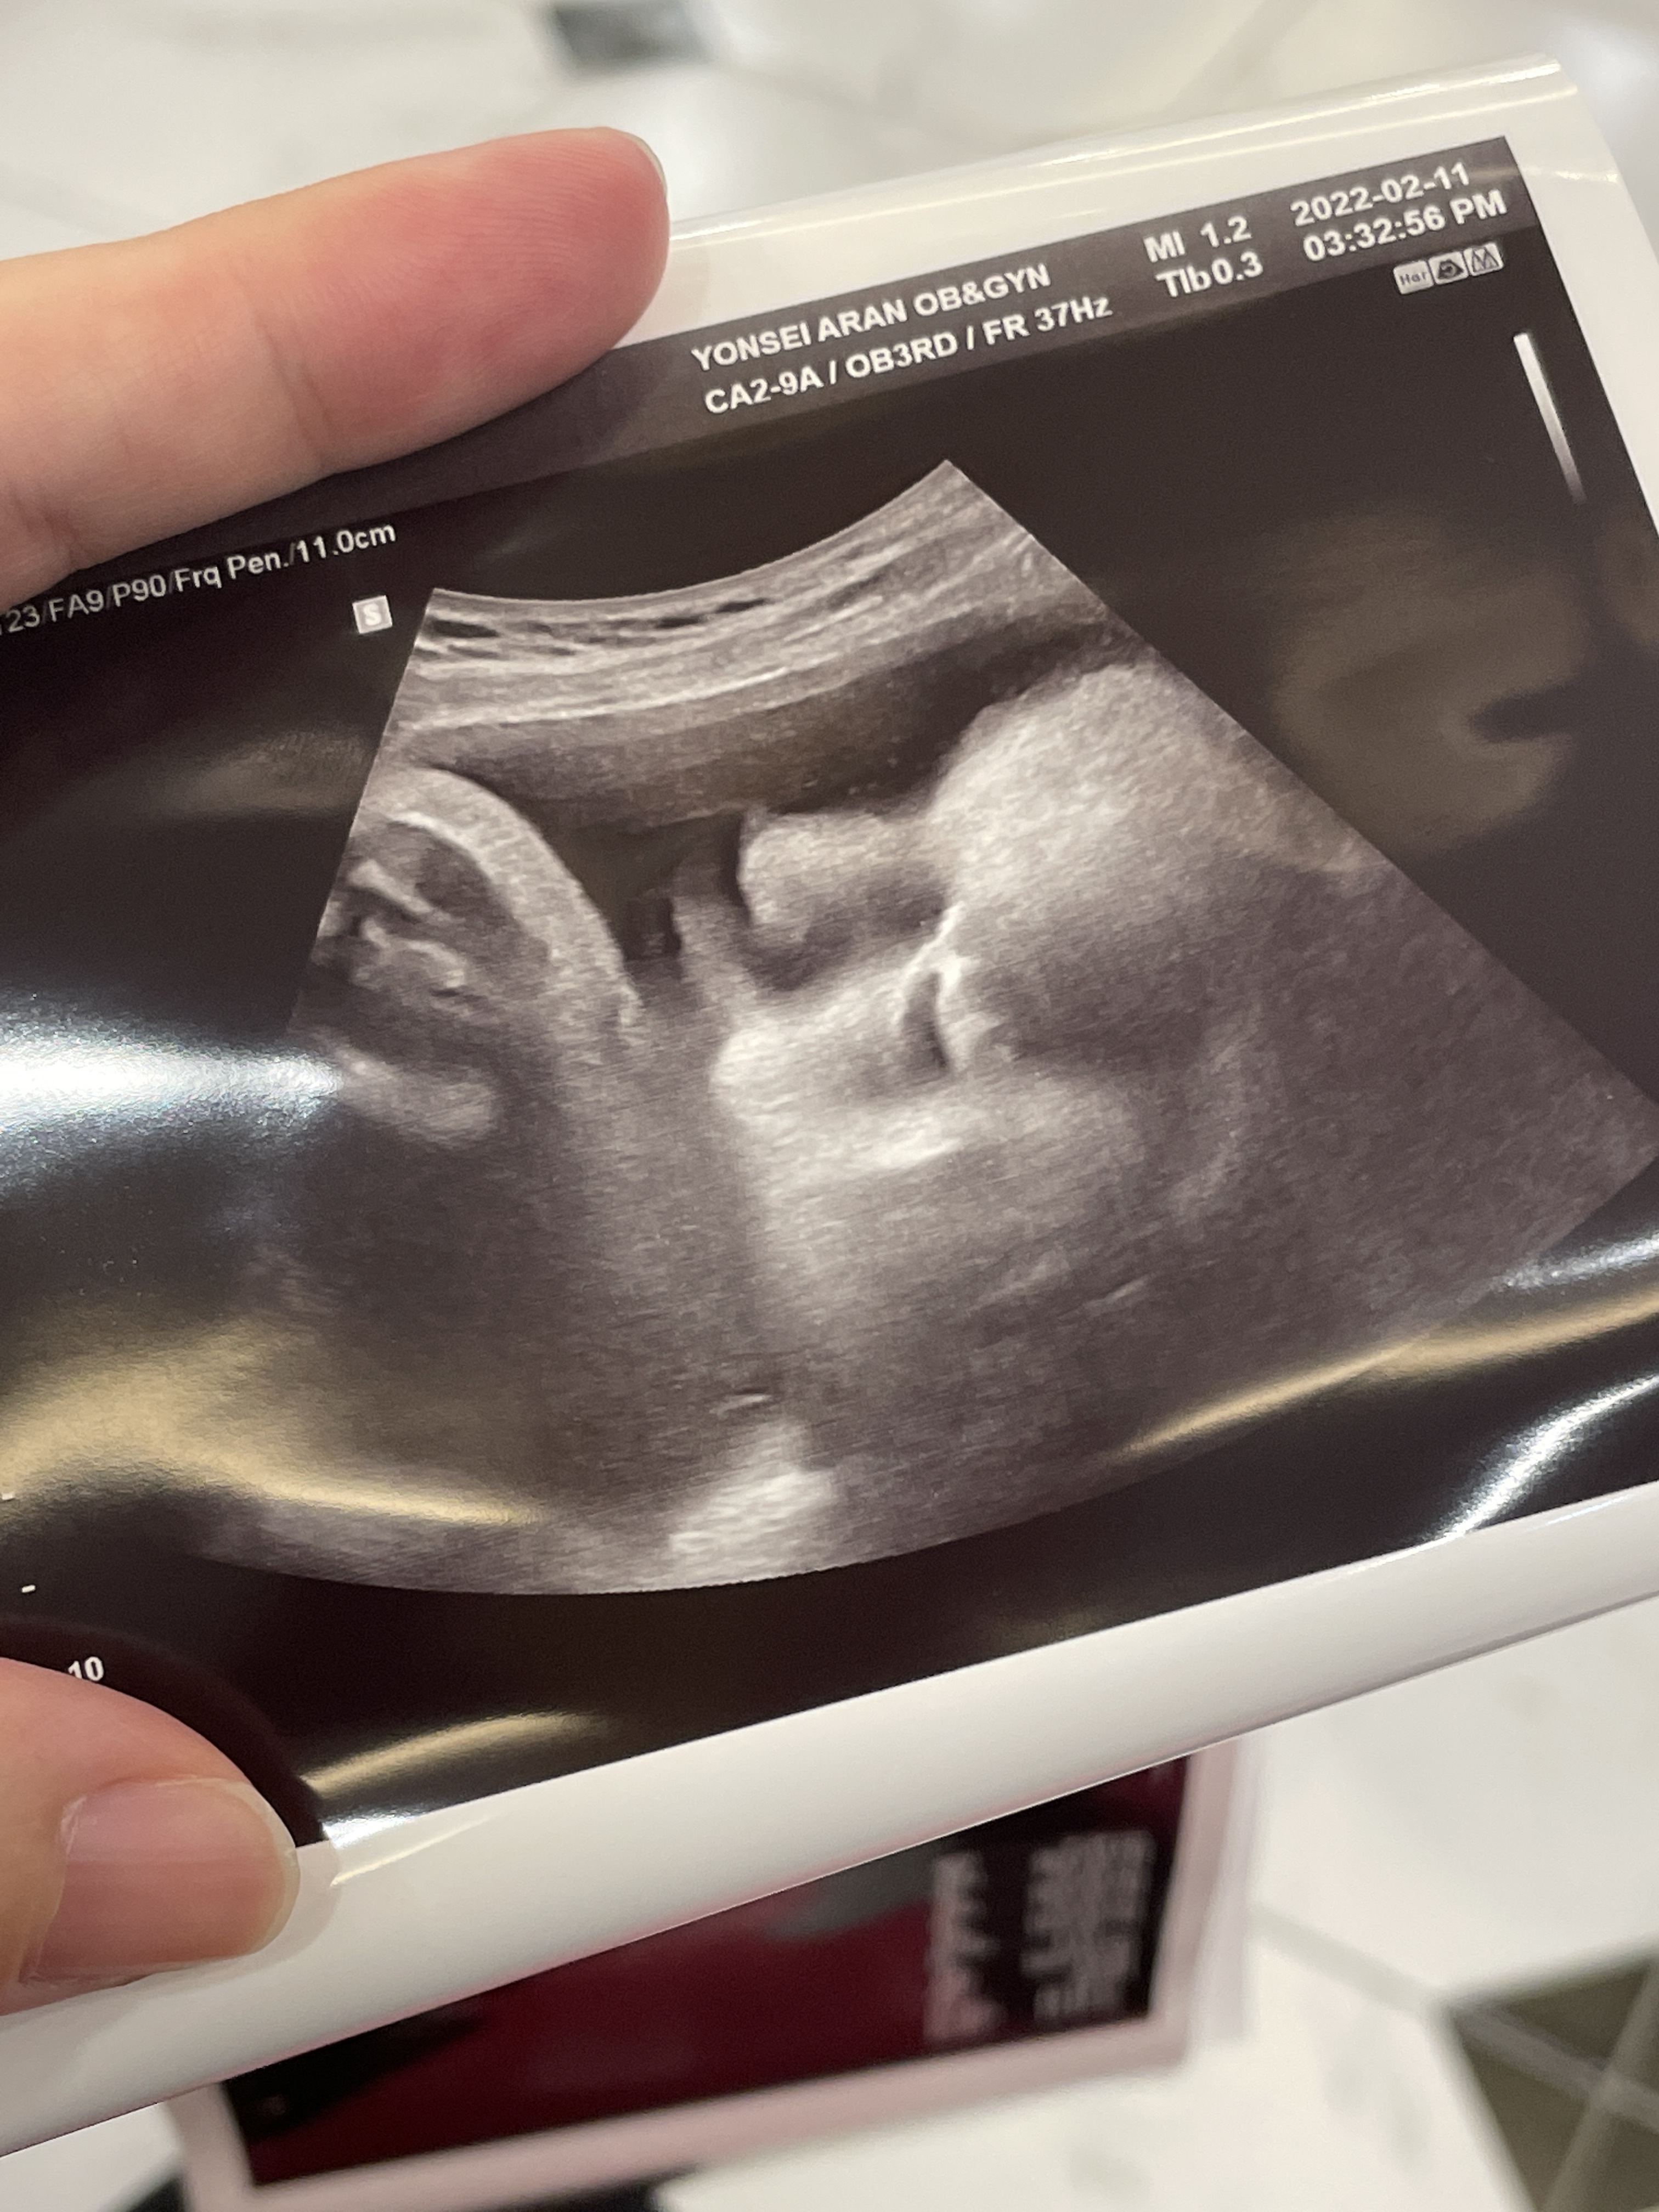

애기가 얼굴이 너무 잘보인다며 웃으셨다.

그와중에 머리는 역시 커졌고,